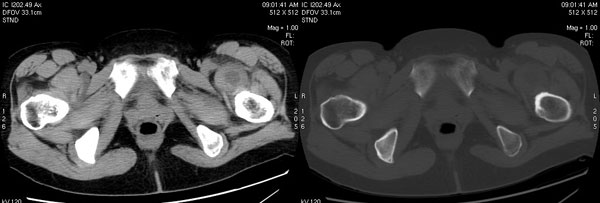

以下是引用jiajie在2006-7-14 17:19:00的发言:[br]ct所见:双侧髋关节不对称,左侧关节间隙变窄,关节面毛糙。左侧股骨头变形、无明显变小,前上缘与髋臼融合,融合处骨质明显增生硬化,并见数个小囊变影。股骨头下端与股骨颈交界部见囊样变,邻近肌肉内见囊样密度减低区,ct值24hu。右侧髋关节形态未见异常。[br][br]ct诊断:左侧髋关节结核可能,请结合临床资料进一步分析。

以下是引用lihuuuu在2006-12-5 10:14:00的发言:[br]定位像示:左侧髋臼变浅,倾斜度加大,髋臼外上缘呈波浪状不规则,骨质增生硬化,髋关节上缘间隙明显变窄,股骨头向外上轻度移位。轴位像示:左侧股骨头变形,前上缘与髋臼融合,融合处骨质明显增生硬化,并见数个小囊变影。股骨头下端与股骨颈交界部见囊样变,邻近肌肉内见密度减低区,ct值24hu,内缘见弧形高密度钙化影。右侧髋关节形态未见异常。[br]ct诊断:左侧髋臼发育不良[br] 左侧股骨头缺血性坏死[br] 左侧肌肉内低密度影伴有高密度钙化-考虑早期骨化性肌炎[br] [br]“我认为在描述上已经写了肌肉部分,印象诊断里应该写主见”[br]